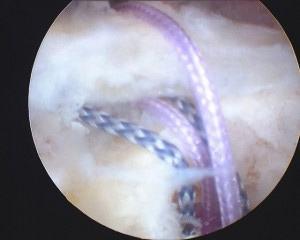

Sutures placed in tendon

Rotator cuff repaired